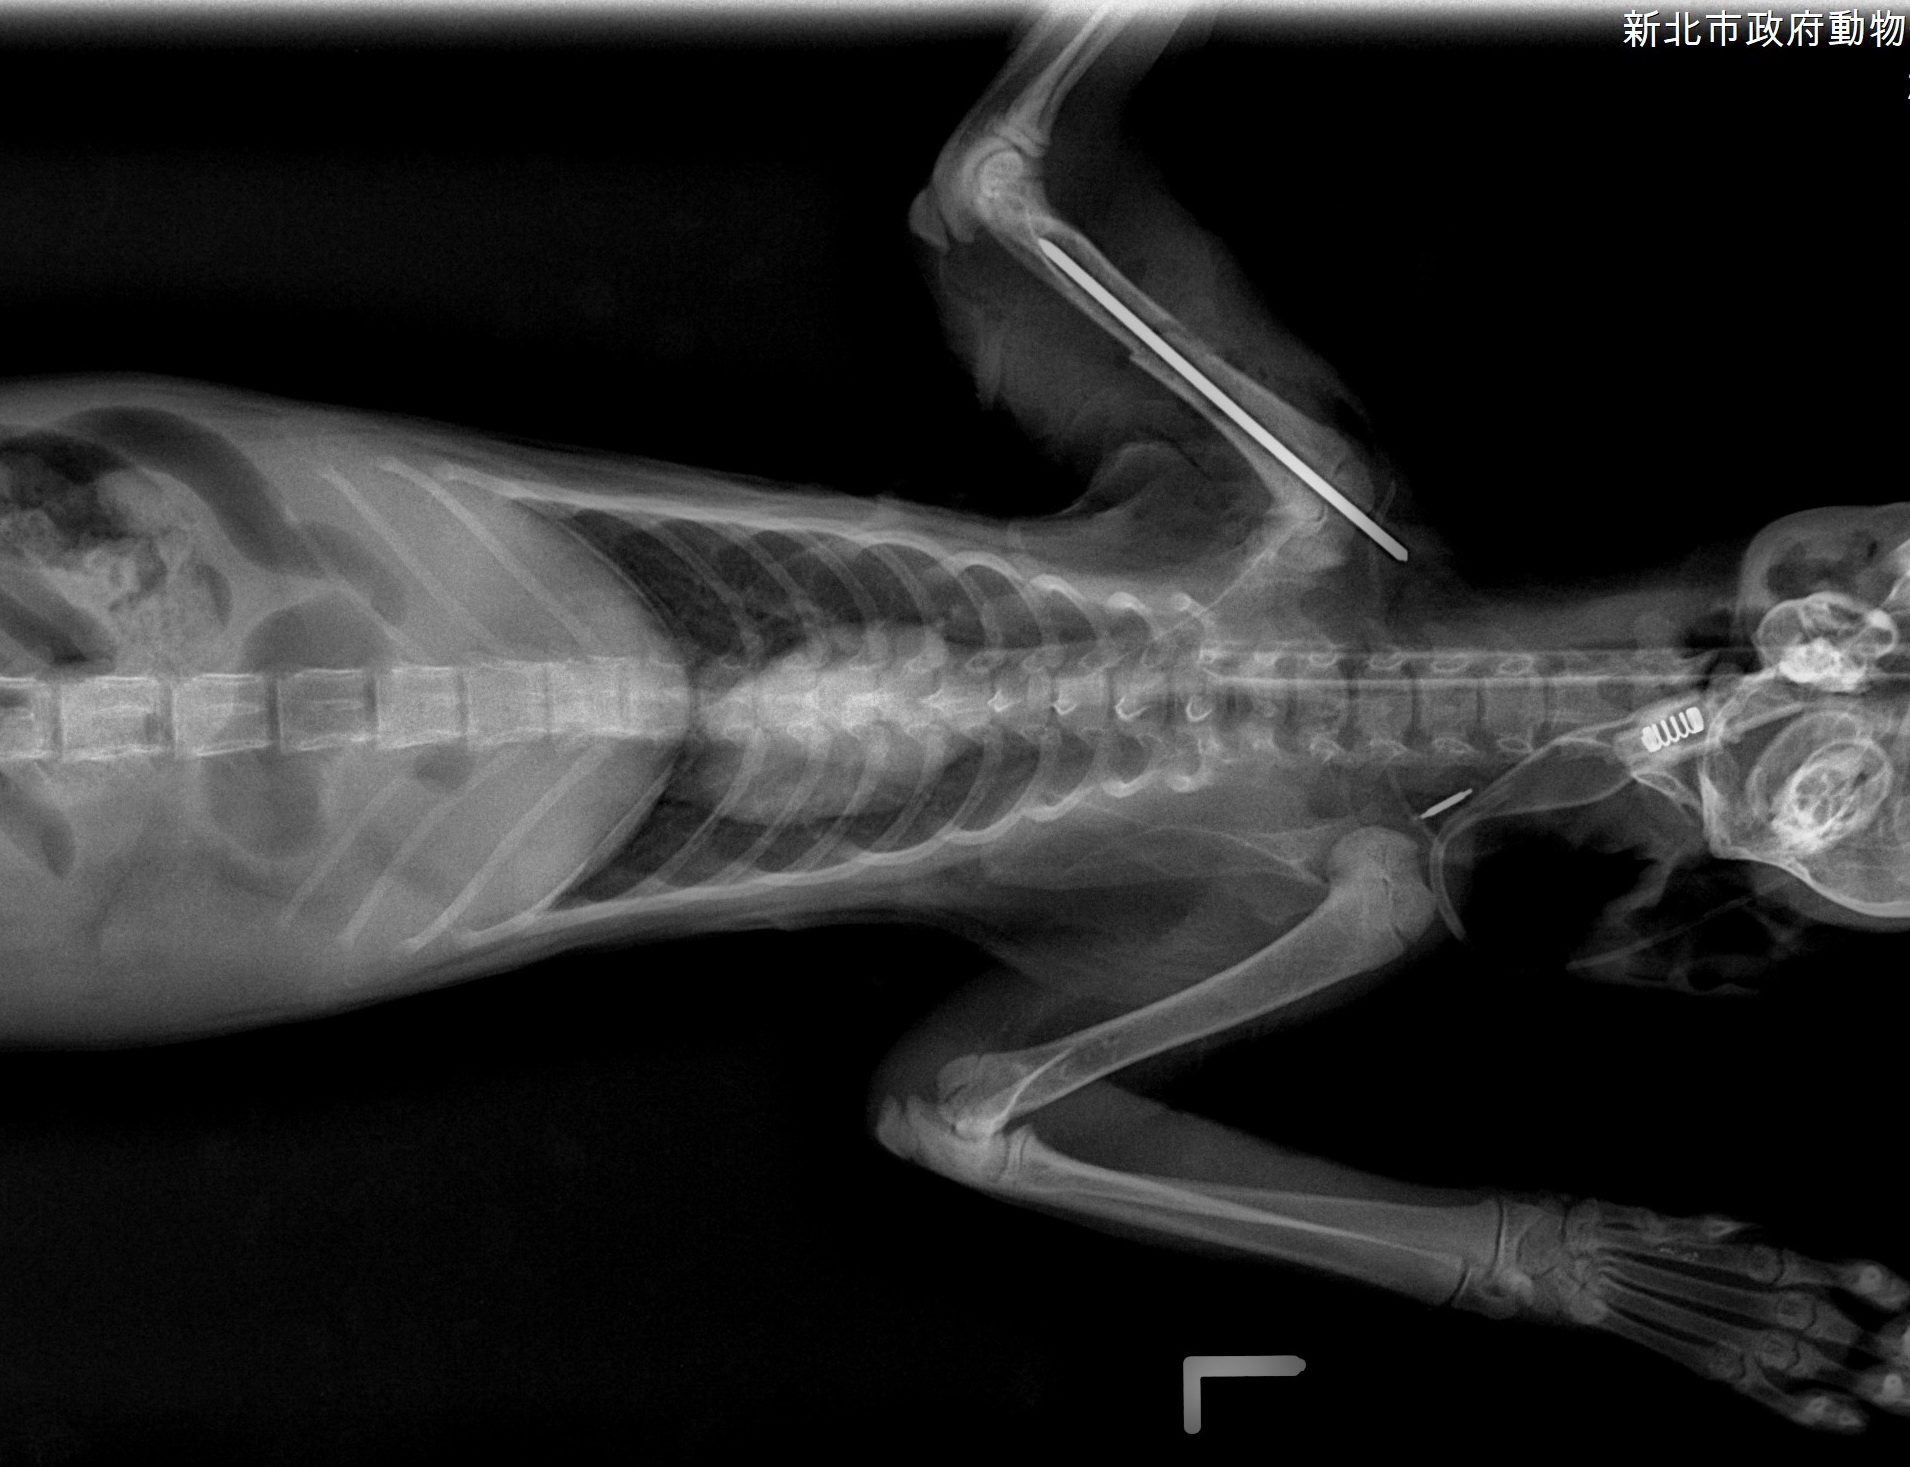

【新北市訊】新北市動保處日前接獲通報新店區安祥路有隻虎斑白貓,疑似車禍受傷臉部充滿血漬癱臥路旁,動保處隨即派員將受傷白虎斑貓帶回毛寶貝醫療中心進行檢傷醫療,經醫療中心李獸醫師檢查後,發現虎斑白貓上顎有傷口、右前肢蜷縮無法撐地,X光檢查下發現右前肢肱骨交錯性骨折,肺部支氣管炎症反應嚴重,應該天氣驟變肺部感染、貓活動力變差不甚由高處摔落或車禍所造成,虎斑白貓經過緊急輸液、給氧及骨科手術治療後已恢復健康,由住在新莊的巫小姐認養,有了幸福溫暖的家。

動保處獸醫師李建沛表示,根據毛寶貝醫療中心傷病動物案例顯示,貓咪常因為高處不甚摔落、車禍而造成不同程度的傷害,尤其以顏面受創及肢體骨折居多,若胸腔受創嚴重造成橫膈破裂,則須緊急進行手術治療才能避免猝死,這隻虎斑白貓研判可能是連日天雨視線不佳遭車輛擦撞,造成前肢肱骨骨折及臉部上顎受創,所幸臉部傷勢不嚴重,骨折部位經過手術治療後已回復行走及跳躍功能,很高興牠找到了幸福溫暖的家。

小虎斑白貓骨折手術後的X光片